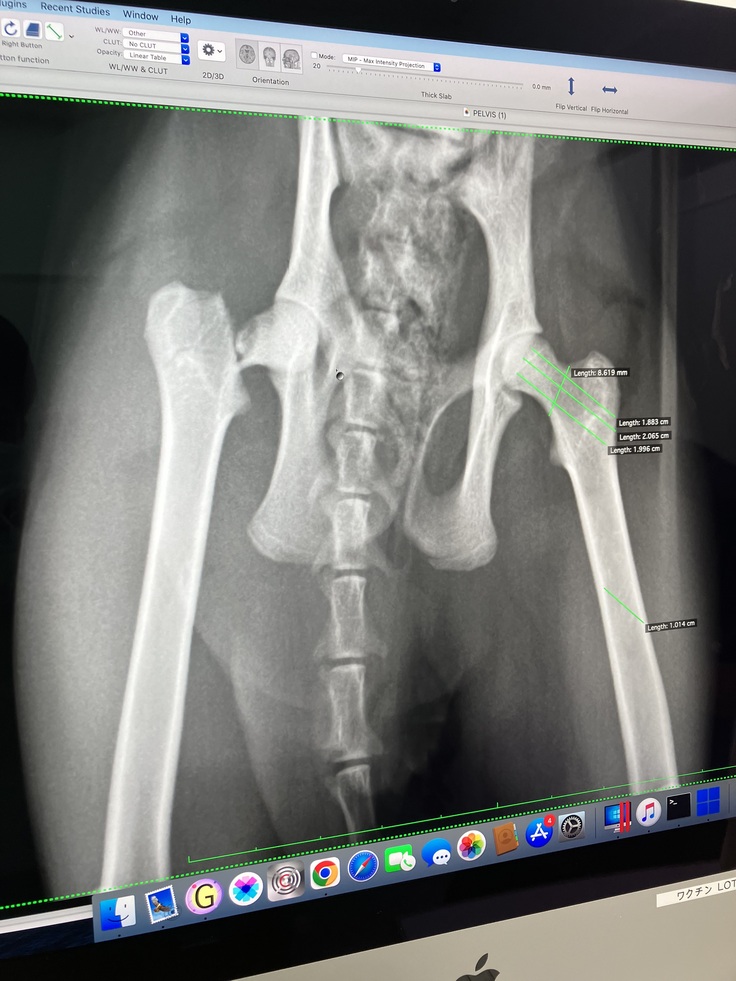

結果は股関節の骨が折れている可能性が高いと

レントゲンの写りが悪く正確なことは伝えられませんが残りの1割の骨で繋がっている状態じゃないかと言われました。先生は熱心な方でしたが

診断結果は、右股関節骨頸部骨折

近年ではよく洋猫に多くあるみたいです

(B病院の診断書、下)

(B病院でのレントゲン写真①②、下)

①

②

手術内容:大腿骨頭骨折整復術